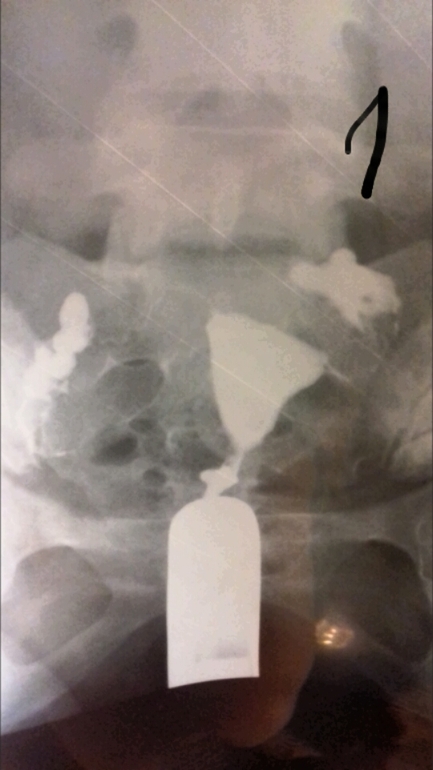

Лапароскопия, гистероскопияДобрый день девочки. Не знаю раздел куда написать, но думаю сюда. Сделала я гсг проверку труб рентгеном. Жидкость прошла, но не сразу, минут так 5 думаю лежала, хотя может меньше. Показало спайки в брюшной полости и вроде как в ампулярных отделах, так как они были расширены при поступлении контраста. И также сказали, что спайки скорее всего из-за эндометртоза. Кто сталкивался с такими проблемами, может подскажите, что по этому и по снимкам.

Полностью согласна. Все эти процедуры ведут только к лапаре. И гистероскопия также проводится в диагностических целях. Ну пробьют они раствором трубы, но это я думаю особой пользы не приносит. На снимках видно, что жидкость изливается в брюшную полость, значит проходимость есть, но если частичная, это уже не то. Так что не тчните, ларара, пару месяцев если еб нет и на Эко.